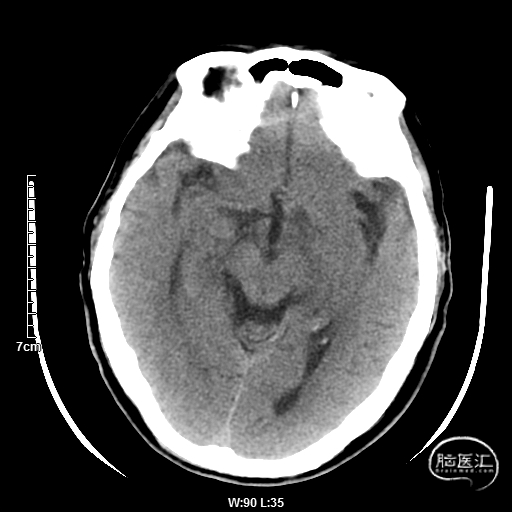

颅脑CT:未见明显缺血/出血病灶。

CTA提示:右侧椎动脉纤细,左侧椎动脉V1、V4段纤细。

MRI提示小脑缺血性改变。